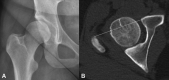

Introduction Adult dysplasia of the hip (ADH) is a disorder of abnormal development of the hip joint resulting in a shallow acetabulum and uncovering of the femoral head. Several radiological measurements such as the Tönnis angle (acetabular index), lateral center edge angle of Wiberg, and cross-sectional imaging parameters exist to calculate hip dysplasia. Aims The aim of this article was to describe a new ancillary linear measure of ADH on cross-sectional imaging, the Birmingham Royal Orthopaedic Hospital (BROH) Femoral offset. Patients and Methods Anteroposterior radiographs of the pelvis and computed tomography imaging of 100 consecutive patients with suspected hip dysplasia were reviewed. Demographic details and clinical indications were recorded. Tönnis angle was utilized to measure hip slope on radiographs and the BROH femoral offset was calculated for each patient. Student's t -test and one-way analysis of variance (ANOVA) were performed. Intraclass correlation coefficient analysis was evaluated to assess the reliability between observers. Results There was a total of 100 patients (128 hips) included in the study (60 with normal Tönnis angle, 53 had dysplasia, and 15 had decreased Tönnis angle). The average BROH femoral offset in the dysplastic cohort was increased in comparison to the normal cohort with a statistically significant p -Value of 0.0001. The p -value was 0.00031 on ANOVA. The BROH femoral offset calculation revealed good intra- and interobserver reliability of 0.9 and 0.9, respectively. Conclusion The BROH femoral offset can be an additional index for measuring ADH that is easier to calculate, and reproducible with good intra- and inter-observer reliability on cross-sectional imaging.